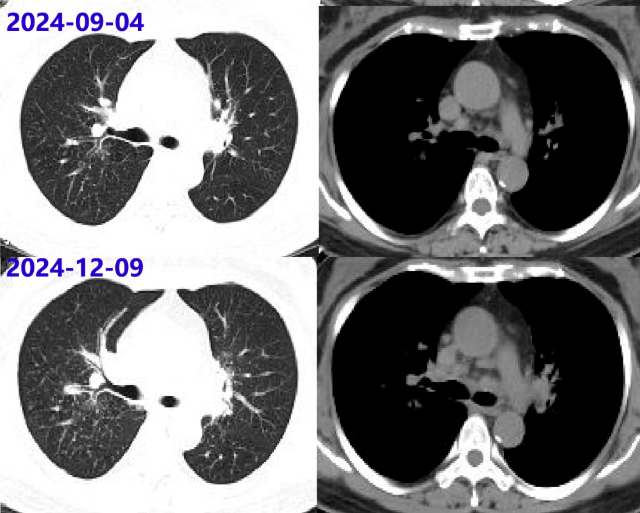

2024-08-26 停用甲泼尼龙。09-04胸部增强CT:两肺门及纵隔多发小及增大淋巴结,较06-12片部分稍大。继续停药。

2024-12-09 胸部CT:纵隔及肺门多发淋巴结肿大,两肺多发病变,均较09-04片进展;ACE阴性。考虑结节病复发,再次启动糖皮质激素治疗,方案:甲泼尼龙32mg qd×1周、28mg qd×2周、24mg qd维持。